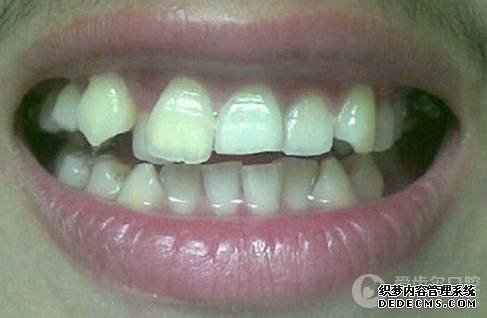

矫正前旧照

矫正前照片